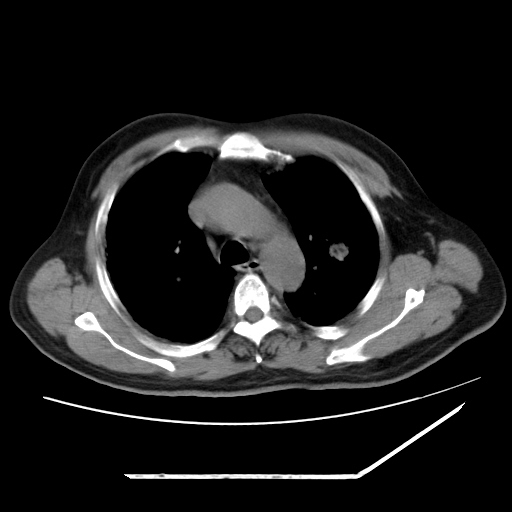

男,57,畏寒,发热

两肺野多发大小不一高密度灶,纵膈内见肿大淋巴结,要考虑转移瘤可能。双侧胸腔少量积液。

双肺多发结节样病灶,部分内见透光区,纵隔内见淋巴结肿大。结核临床如有畏寒,高热,白细胞增高首先考虑迁徙性肺脓肿(多是金黄色葡萄球菌感染)。

注意除外转移瘤。

1)考虑两肺感染性病变(金黄色葡萄球菌肺炎?);建议抗炎治疗后复查排除其他。2)双侧少量胸腔积液。